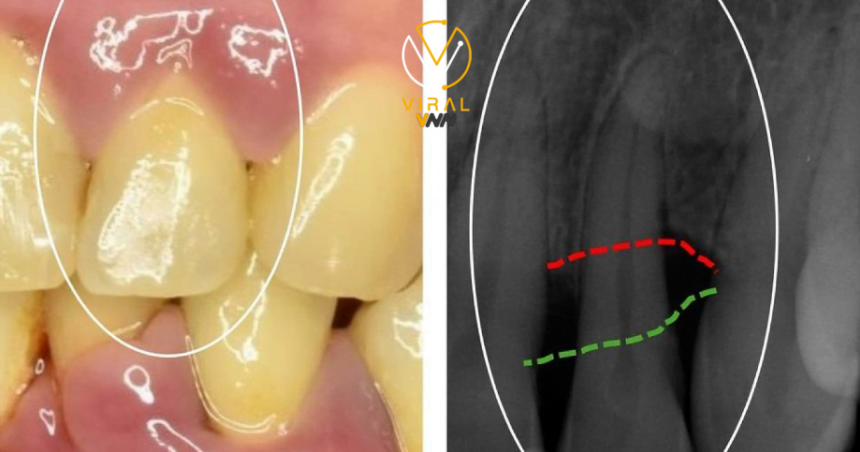

يعد التهاب اللثة مرضاً مزمناً يصيب الأنسجة المحيطة بالأسنان، مما يؤدي إلى تهيجها واحمرارها وتورمها ونزيفها،

نتيجة تراكم طبقة لزجة تعرف بـ “البلاك” التي تتكون أساساً من البكتيريا.

ومع مرور الوقت، يمكن أن يتصلب البلاك ويتحول إلى “جير”، مما يسبب تهيجاً أكبر في الأنسجة وإنتاج فجوات عميقة بين الأسنان واللثة التي تزدهر فيها البكتيريا.

في حالات التهاب اللثة الشديدة، قد يؤدي المرض إلى تآكل الأنسجة الداعمة للأسنان وفقدانها.